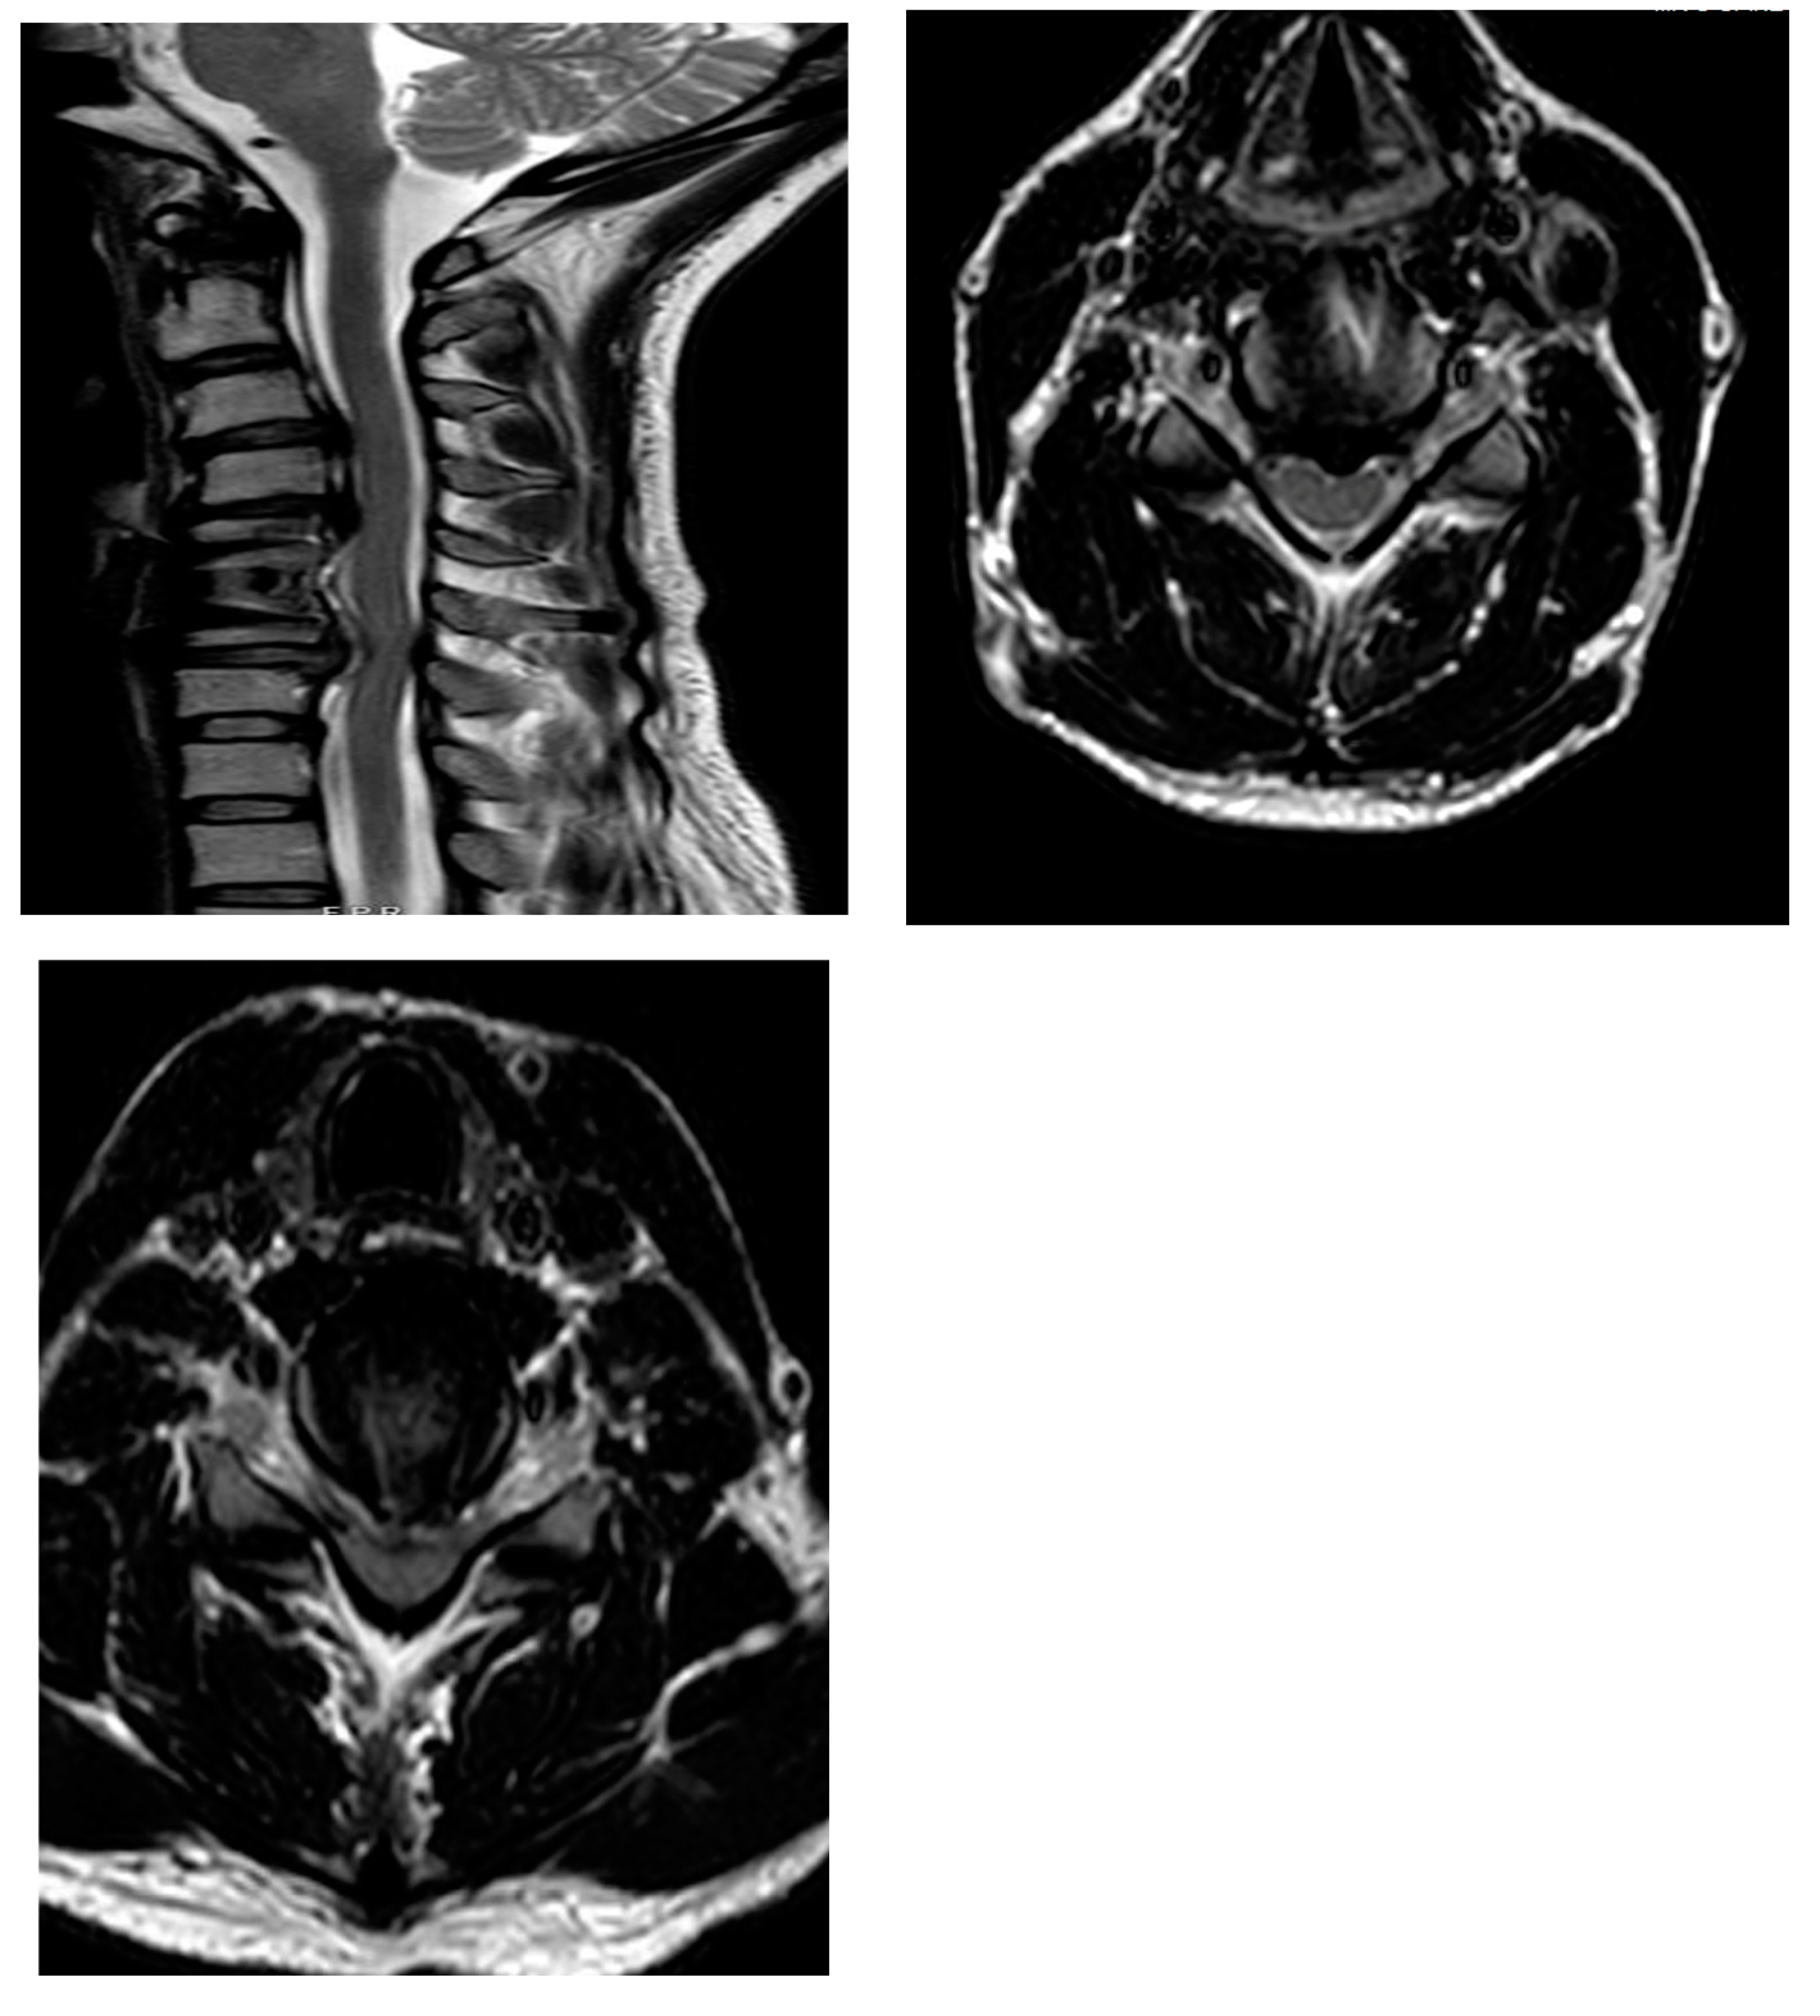

2.1. Case 1